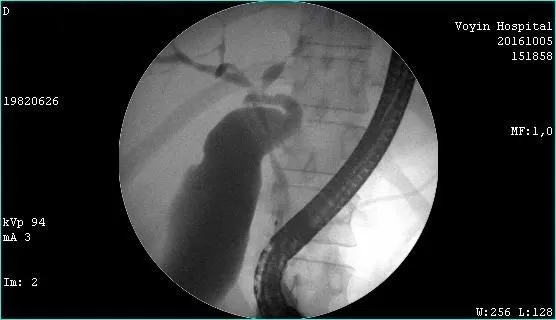

Молодой человек 33 г. Диагноз подтвержден. Стентирован пластиковыми стентами, потом самораскрывающимися. Одномоментно анте и ретроградно - с хорошим результатом. Дальше был поставлен в очередь на трансплантацию. Дальнейшая судьба не известна.